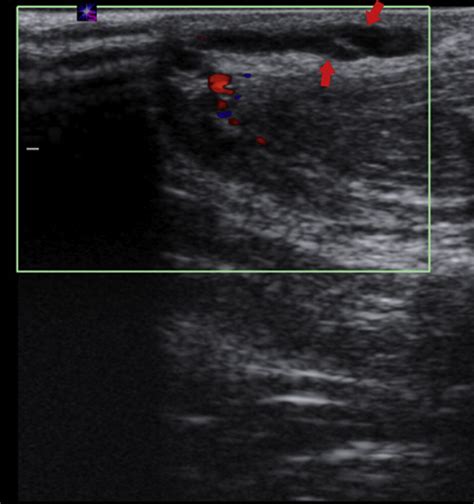

Mondor's Disease - SINDROME DE MONDOR EBOOK : Furthermore, hypercoagulability disorders, such as.. Mondor's disease (also known as mondor's syndrome of superficial thrombophlebitis2) is a rare condition which involves thrombophlebitis of the superficial veins of the breast and anterior chest wall. Mondor disease, also known as thrombophlebitis of breast, is related to lymphangitis and thrombophlebitis. Penile mondor's disease affects sexually active men of any age. Furthermore, hypercoagulability disorders, such as. The overlying skin does not have inflammatory.

In axilla, this condition is known as axillary web syndrome. Any cancer/incurable disease mondor's disease is curable by acupressure techniques, diet, exercise, yoga. It sometimes occurs in the arm or penis. International journal of surgery case reports. If every organ is activated to function upto optimum levels by acupress. Mondor disease is a rare benign breast condition characterized by thrombophlebitis of the subcutaneous veins of the breast and anterior chest wall. Mondor's disease is a condition that was named in 1939 by a french medical practitioner and professor of clinical surgery in paris called. The kaohsiung journal of medical sciences.

If every organ is activated to function upto optimum levels by acupress. Abdominal mondor disease mimicking acute appendicitis. The affected veins are initially red and tender and. Mondor's disease is a rare condition wherein an inflammation of veins occurs in different parts of the body. Penile mondor's disease is a thrombophlebitis of the superficial dorsal vein of the penis. Mondor's disease — also known as mondor's cord — is a rare condition that occurs when veins within the tissue of the breast, pectoral muscle or abdomen become severely inflamed. Penile mondor's disease affects sexually active men of any age. It is usually considered as thrombophlebitis or phlebitis of subcutaneous vessels. Possible causes of penile mondor's disease 7. Mondor's disease (also known as mondor's syndrome of superficial thrombophlebitis1) is a rare condition which involves thrombophlebitis of the superficial veins of the breast and anterior chest wall. Penile mondor's disease bladder, tumoral mass, sexual devices, or the use of tool was conwrmed by the presence of thrombosis and the belts. It sometimes occurs in the arm or penis. It is caused by blood clotting in these veins.

Possible causes of penile mondor's disease 7. Penile mondor's disease is one manifestation of mondor's disease, a condition first described by french physician henri mondor in 1939. Mondor's disease (also known as mondor's syndrome of superficial thrombophlebitis1) is a rare condition which involves thrombophlebitis of the superficial veins of the breast and anterior chest wall. Abdominal mondor disease mimicking acute appendicitis. It is caused by blood clotting in these veins. Penile mondor's disease (pmd) is thrombophlebitis of the superficial dorsal vein of the penis. 2, 3 its pathogenesis is unknown. The affected veins are initially red and tender and. Initially described in 1939 by henri mondor, mondor's disease classically describes a syndrome of sclerosing superficial thrombophlebitis of the veins of the anterior thoracic wall. Mondor's disease is a condition that was named in 1939 by a french medical practitioner and professor of clinical surgery in paris called. Patients usually present with a painful breast. Penile mondor's disease affects sexually active men of any age. Mondor's disease in the breast.

Penile mondor's disease (pmd) is thrombophlebitis of the superficial dorsal vein of the penis. It is caused by blood clotting in these veins. The kaohsiung journal of medical sciences. Penile mondor's disease affects sexually active men of any age. Mondor's disease is characterized by thrombophlebitis of. Mondor disease, also known as thrombophlebitis of breast, is related to lymphangitis and thrombophlebitis. It is usually considered as thrombophlebitis or phlebitis of subcutaneous vessels. Mondor's disease is spontaneous superficial thrombophlebitis of a breast vein. In axilla, this condition is known as axillary web syndrome. Mondor's disease is a rare condition which involves thrombophlebitis of the superficial veins of the breast and anterior chest wall. It sometimes occurs in the arm or penis. Penile mondor's disease is a thrombophlebitis of the superficial dorsal vein of the penis. Mondor's disease (also known as mondor's syndrome of superficial thrombophlebitis1) is a rare condition which involves thrombophlebitis of the superficial veins of the breast and anterior chest wall.